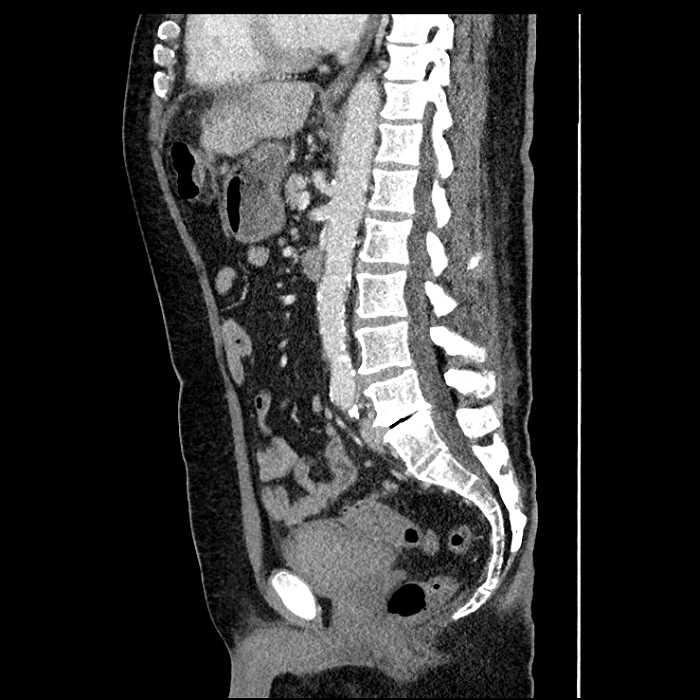

• High grade stenosis of the left common iliac artery, with the left internal and external iliac arteries remaining patent

• Ankylosis of both sacroiliac joints

High grade stenosis of the left common iliac artery. The left external and internal iliac arteries are patent.

Hepatic abscess showing the double target sign with low density internally surrounded by a thin inner enhancing rim (red arrow) and ill-defined outer low density rim (yellow arrow). Blue arrow indicates an internal septation. Red arrows: additional smaller subcapsular abscesses. Red arrow: focal contained perforation associated with diverticulitis.